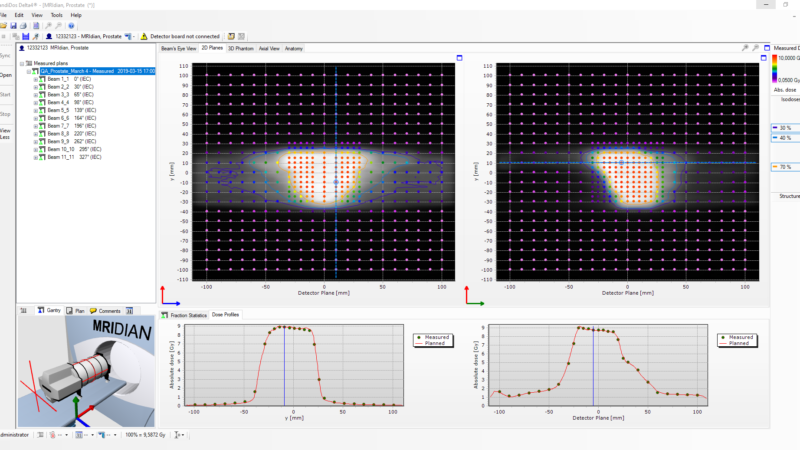

Delta4 software

Streamline your workflow

Delta4 software

Instant and accurate analysis

- Instant results in one place

- Powerful analytic tools

- Isocentric measurements in two orthogonal detector planes

- Resolution 5 mm at isocenter, can be increased to 2.5 mm by merging